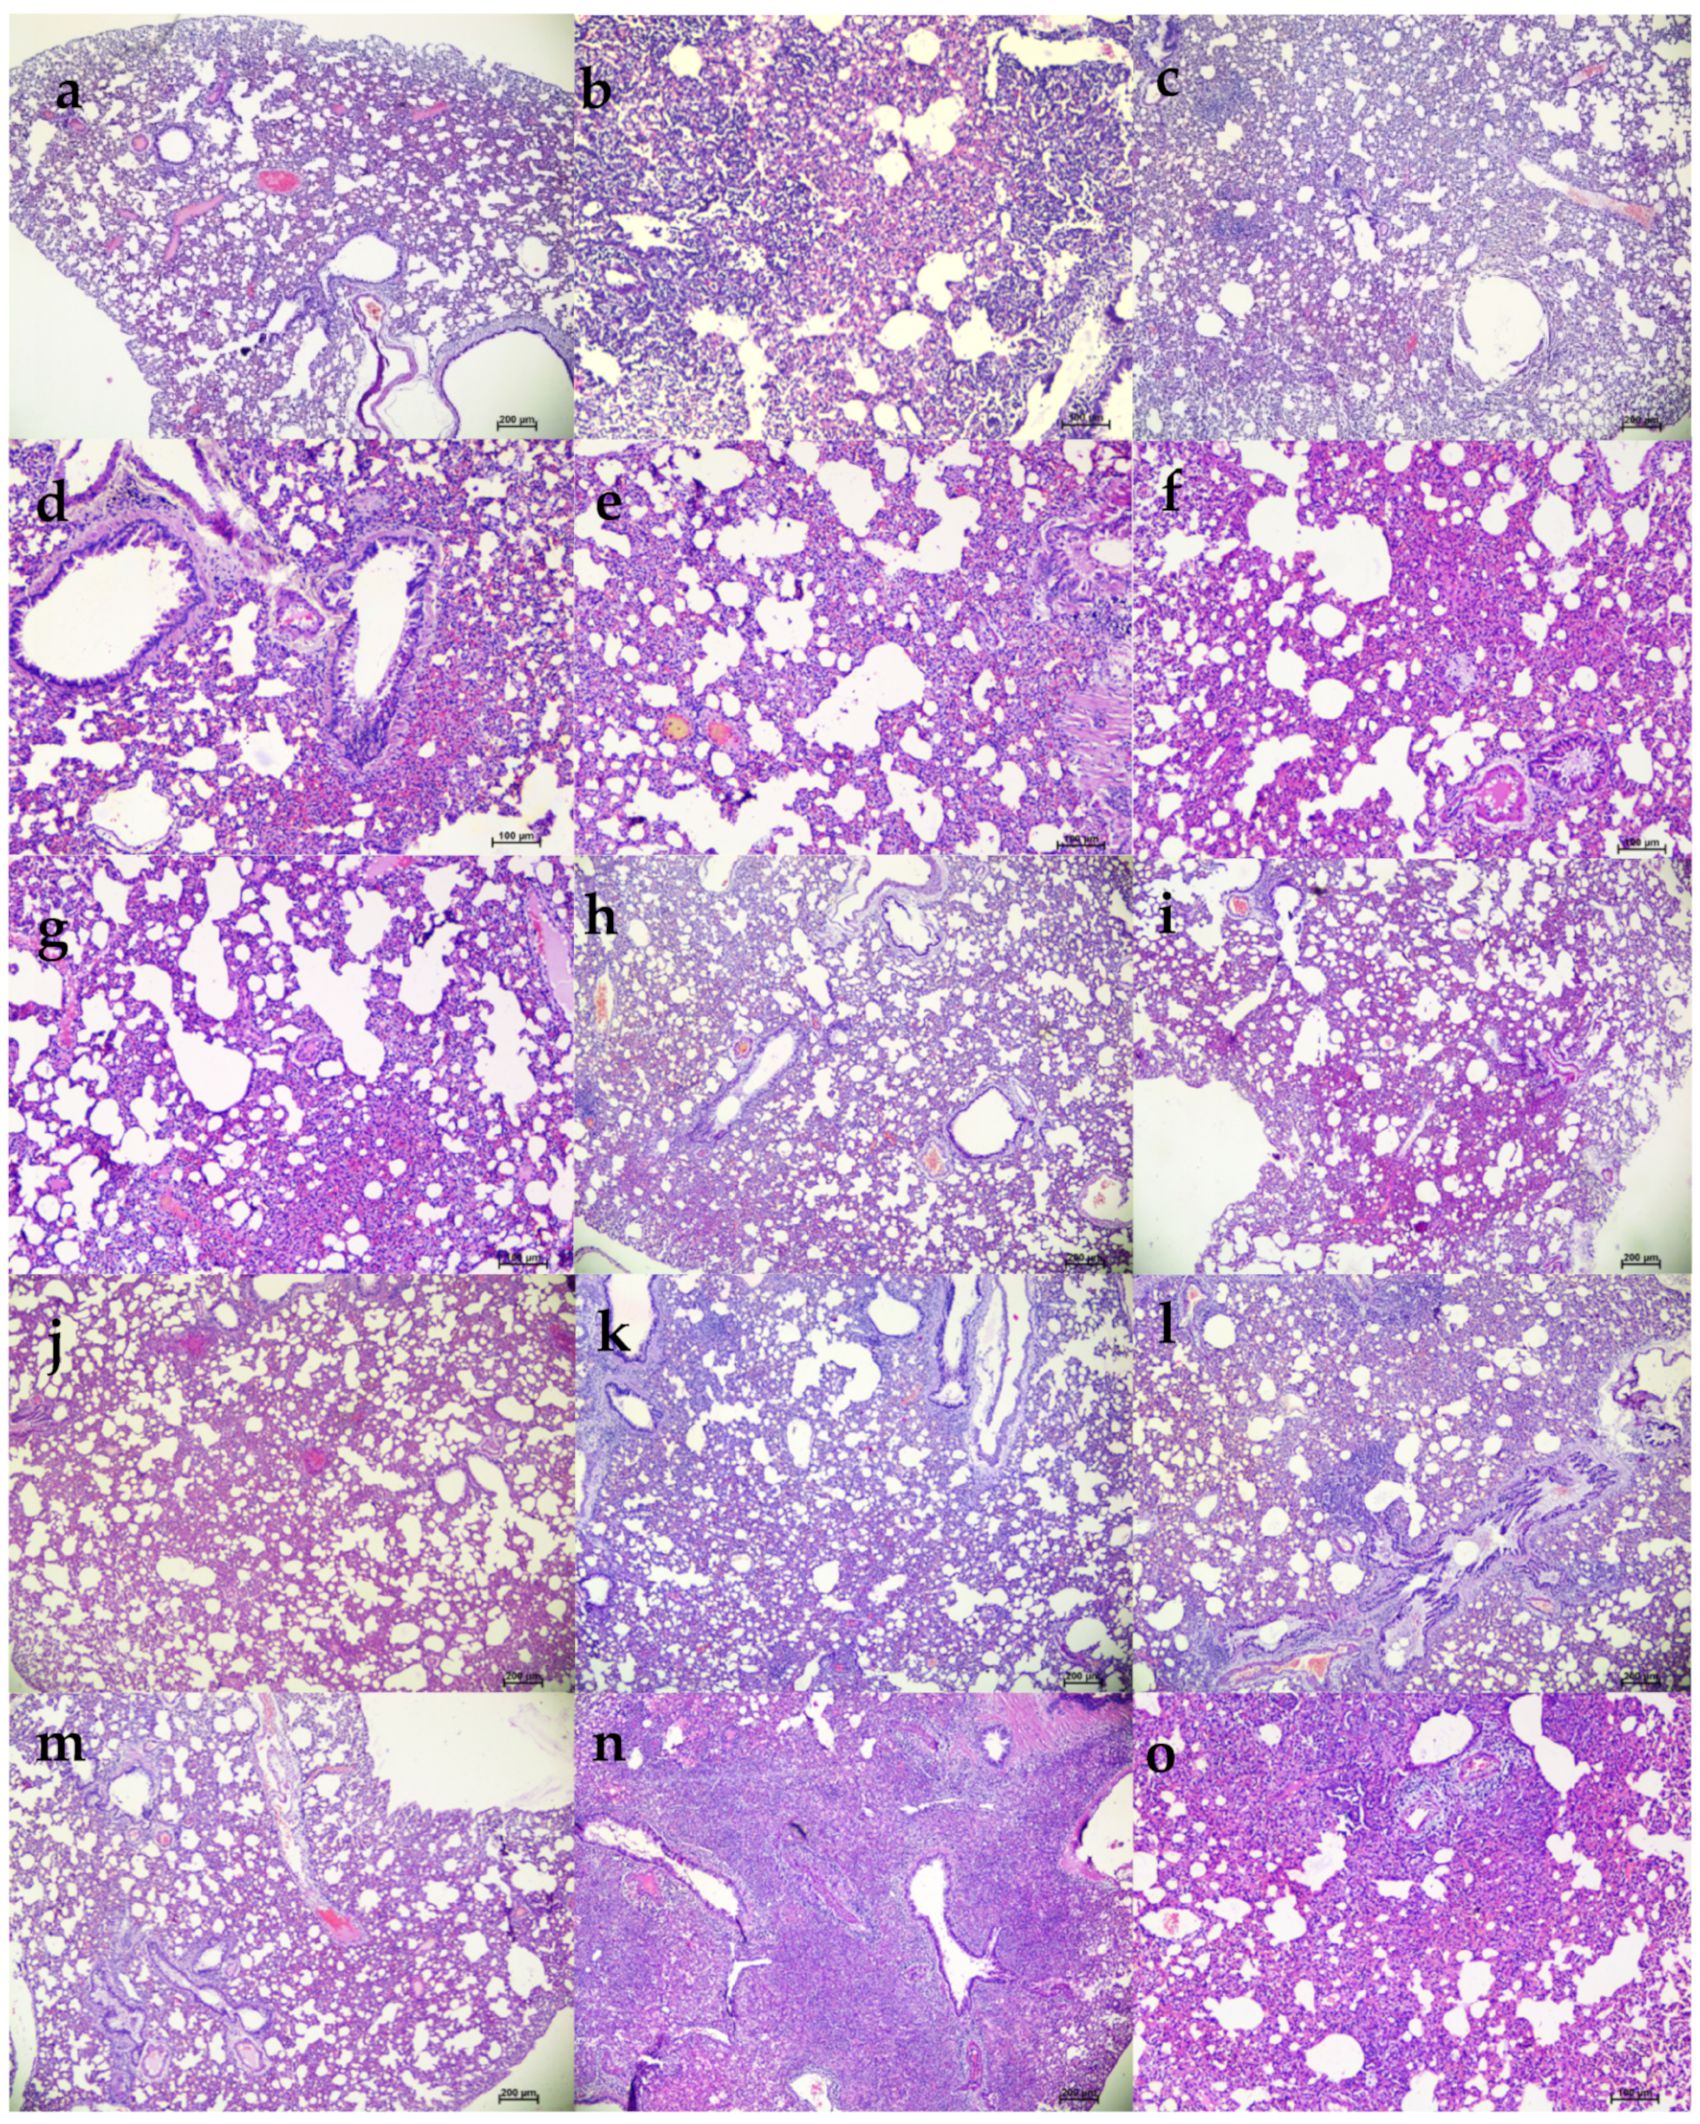

In the 103.5 TCID50 virus dose group, only minimal bodyweight reduction was seen in the 50 and 5 mg/kg mAb-treated group (Figure 8a,b). The 50 mg/kg group showed consistent viral load reduction on 3 and 5 DPI in nasal wash (p < 0.05), lungs (p < 0.05) and nasal turbinates (p < 0.05) (Figure 8c–e). SgRNA levels in the lungs (p < 0.05) and nasal turbinates (p < 0.05) also were significantly lower compared to the placebo group (Figure 8f,g). On histopathological examination, mild to moderate changes were seen in the 50 mg/kg dose group with a lower histopathological score, whereas the hamsters of the 5 mg/kg group and placebo group showed comparable disease severity (Figure 8h and Figure 9).

Figure 9.

Histopathological changes in lungs of hamsters that received mAb therapy 24 h post infection with 103.5 TCID50. Lungs of hamsters of 50 mg/kg dose group on 5DPI showing (a) engorged alveolar capillaries, (b) emphysematous changes, (c) consolidation and mononuclear cell infiltration, (d) foci of alveolar capillary congestion, and (e) alveolar septal thickening, scale bar = 100 µm. Lungs of hamsters of the 5 mg/kg dose group on 5DPI showing (f) focal areas of congestion and septal thickening, (g) peribronchial inflammatory cell infiltration and foci of consolidative changes, (h) diffuse inflammatory cell infiltration in the alveolar paranchyma, (i) diffuse alveolar changes and congestion, and (j) diffuse alveolar septal thickening, scale bar = 100 µm. Lungs of placebo group on 5DPI showing (k) diffuse inflammatory cell infiltration in the peribronchial area, (l) peribronchial inflammatory cell infiltration and alveolar septal thickening, (m) diffuse alveolar consolidation and inflammatory cell infiltration, (n) foci of mononuclear cell infiltration and septal thickening, and (o) diffuse alveolar septal thickening and congestive changes, scale bar = 100 µm.